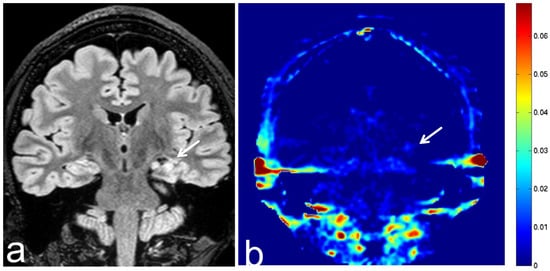

8.5. Hippocampal Sclerosis